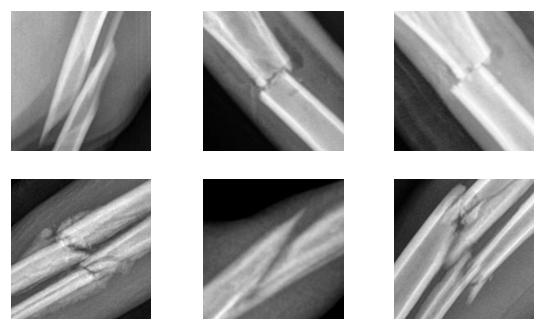

A qualitative evaluation was conducted to ascertain the practical relevance and justifiability of the mistakes made by the original production classifier. A sampling of the low SCA-value images from each cluster was reviewed by expert radiologists based on whether the highlighted regions were justifiably located for fracture assessment. Figure 4 shows an example of low-SCA crops for each cluster to illustrate this process. Note that not all clusters contain over 8 low-SCA crops for the display.

The expert radiologists provided their assessments on the nature of the mistakes and the relevance of the identified fractures. For instance, it was unanimously agreed that all the fractures identified in cluster 0 were of interest and held significant value for the business production scenario, particularly with respect to aiding accurate and trusworthy fracture diagnosis. The aberrant predictions rate was below 1% for cluster 3 and below 5% for clusters 2 and 5. Clusters 4 and 1 contain most of the aberrant predictions with 81% for cluster 4 and 25% for cluster 1.